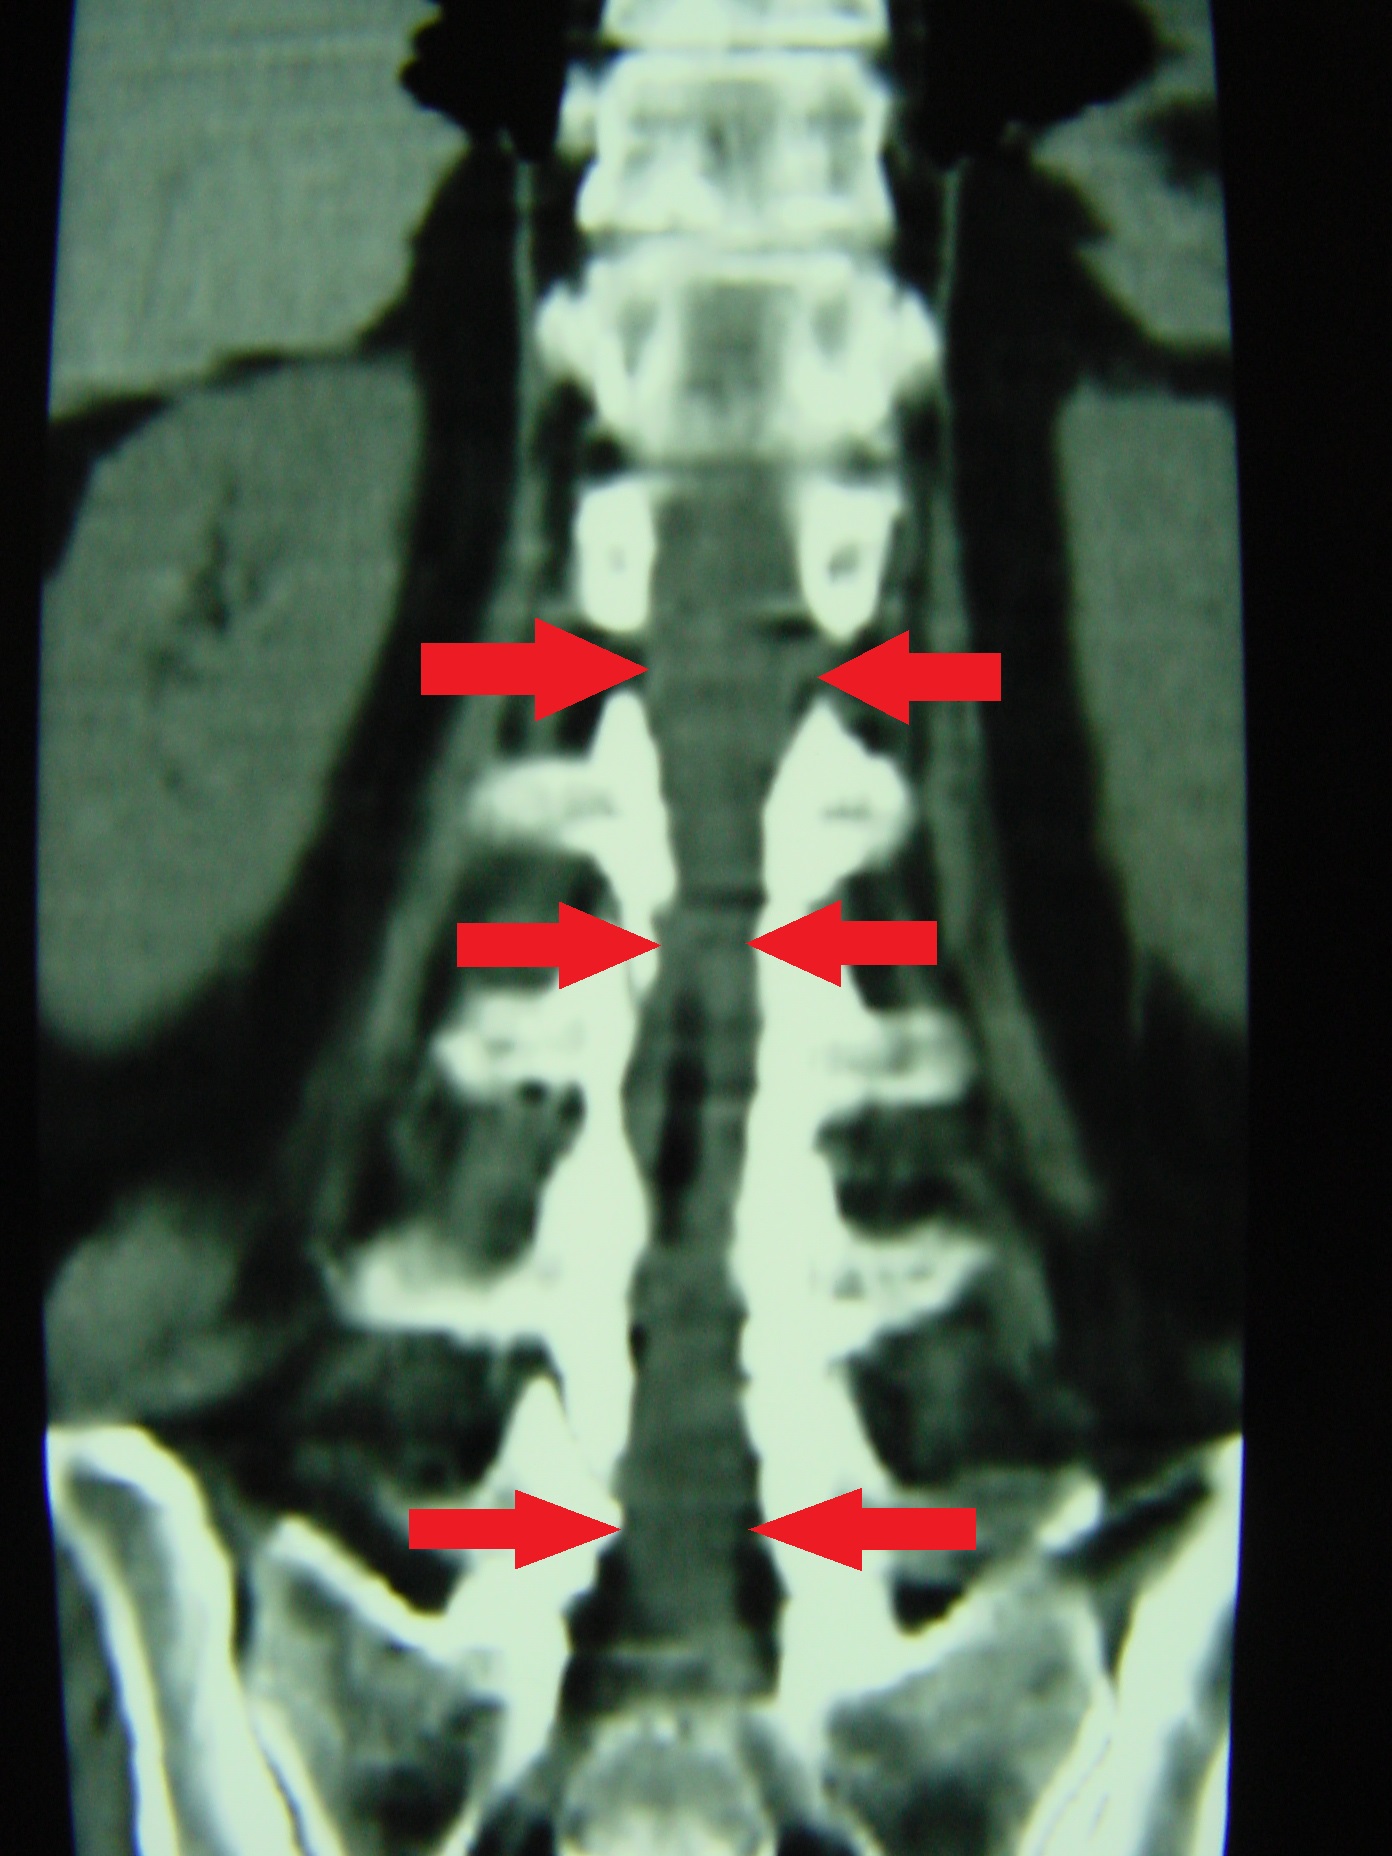

• Echinococcus – Εχινόκοκκος

DSC00013_bakas_echinococos